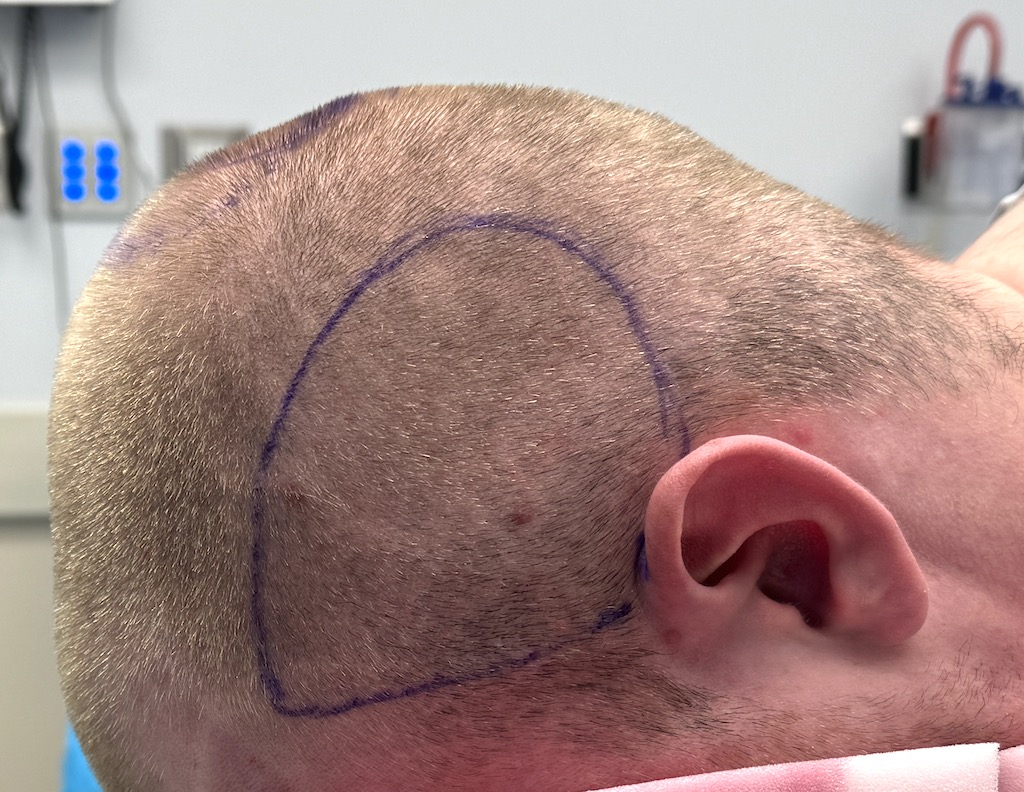

Desire for large overall skull augmentation procedure. Two piece custom skull implant designed with 250ccs volume.

1st stage scalp expander placed and inflated to 225ccs. 2nd stage two piece skull implant placed 4 months later.

Desire for large overall skull augmentation procedure. Two piece custom skull implant designed with 250ccs volume.

1st stage scalp expander placed and inflated to 225ccs. 2nd stage two piece skull implant placed 4 months later.